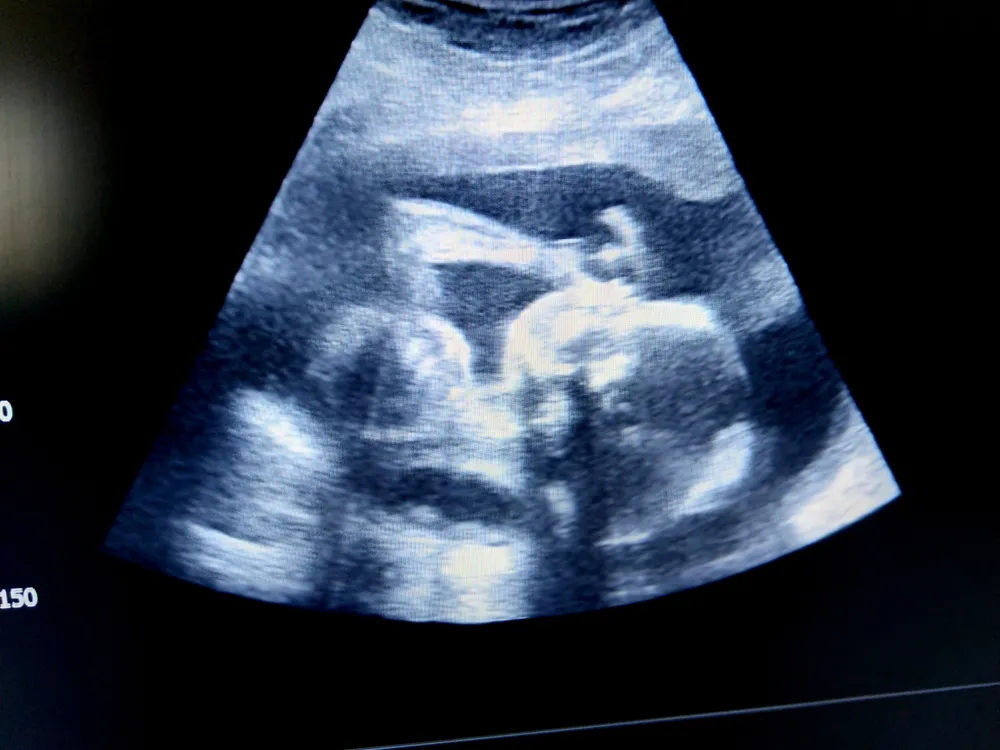

2. Hình ảnh thai nhi 26 tuần trong bụng mẹ

Các chỉ số sinh trắc của thai nhi 26 tuần cụ thể như sau:

- Đường kính lưỡng đỉnh (BPD): 59-72mm

- Chu vi vòng đầu (HC): 225-262mm

- Chu vi vòng bụng (AC): 196-241mm

- Chiều dài xương đùi (FL): 43-52mm.